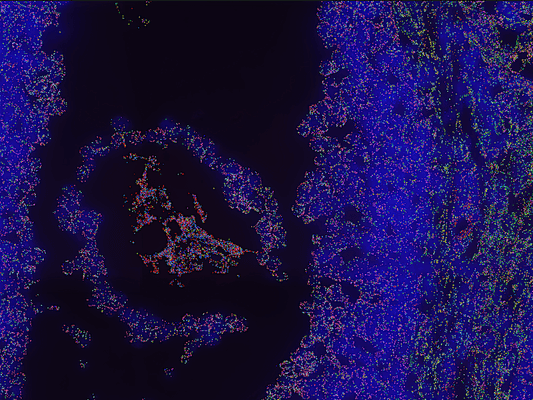

Composite image of an ovarian follicle with an oocyte in the center, showing expression of genes (each spot) in cells (stained blue). (Image by Rhea Sharma and Ruixu (Rachel) Huang)